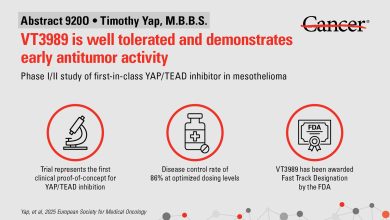

VT3989 continua a mostrar resultados iniciais promissores em pacientes com mesotelioma avançado

Principais dados do estudo do VT3989. Crédito: MD Anderson Cancer Center da Universidade do Texas O primeiro inibidor YAP-TEAD da…